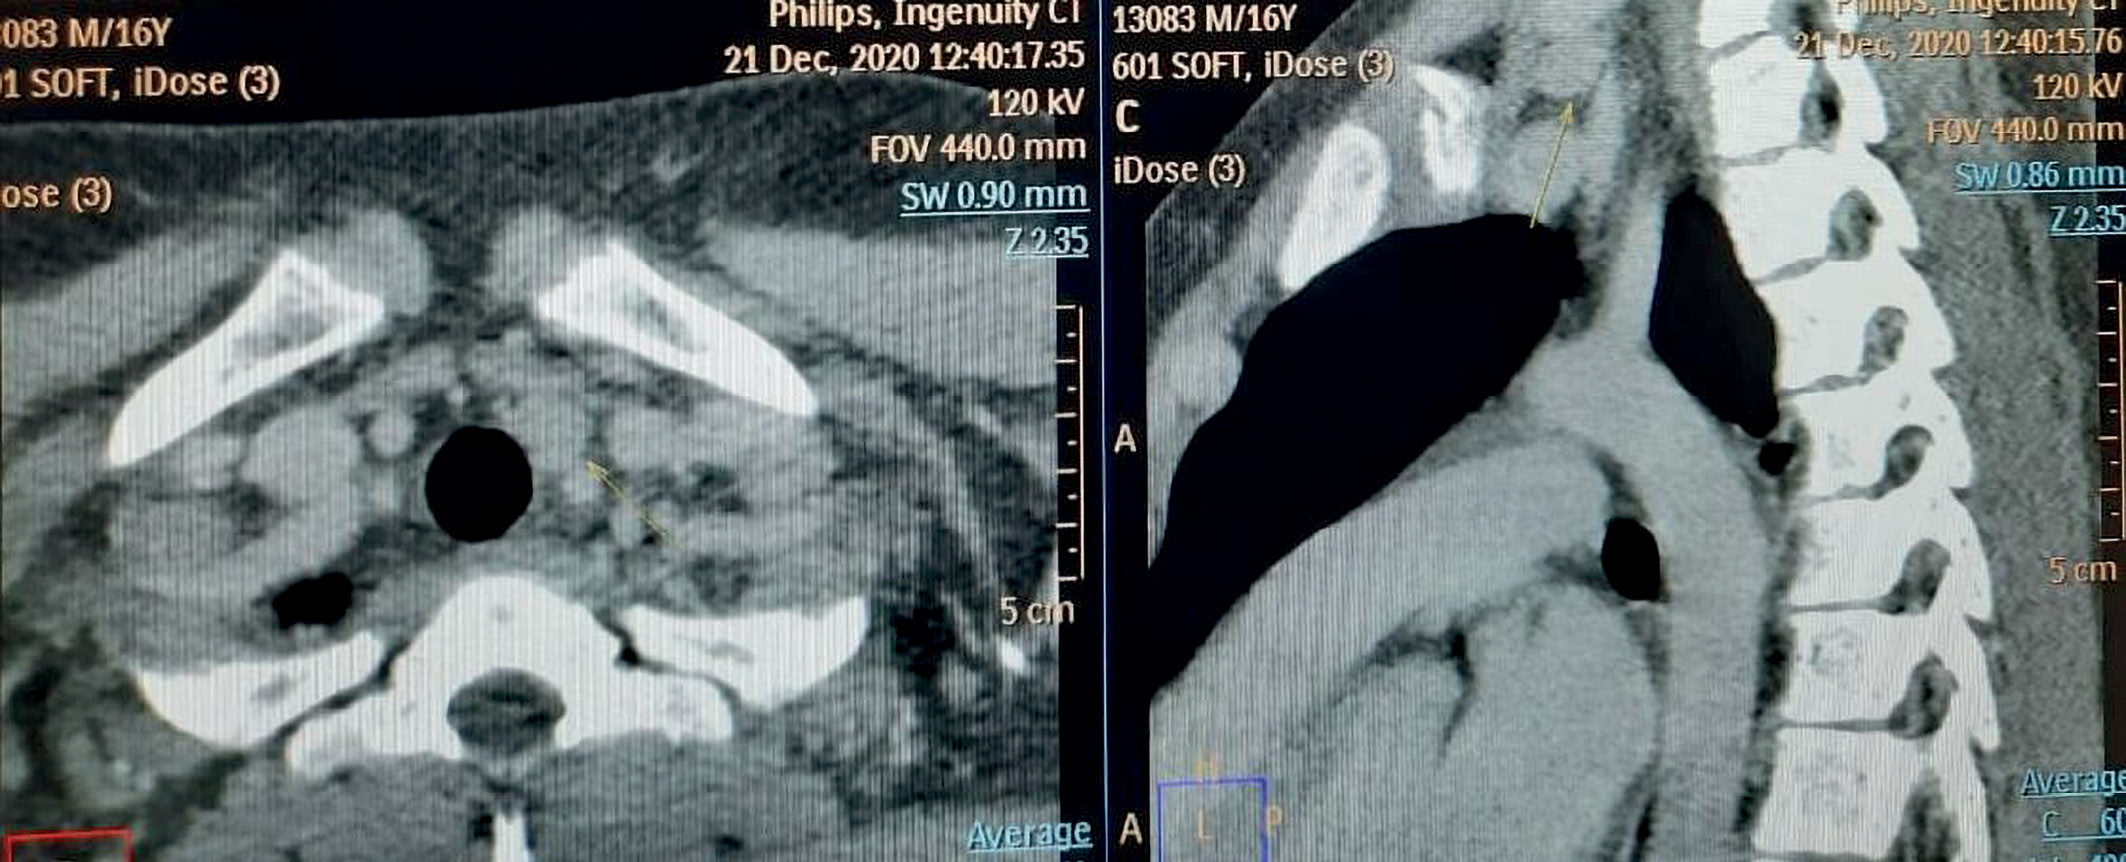

3. Рис. 3. Компьютерная томограмма шеи: стрелкой обозначена аденома околощитовидной железы